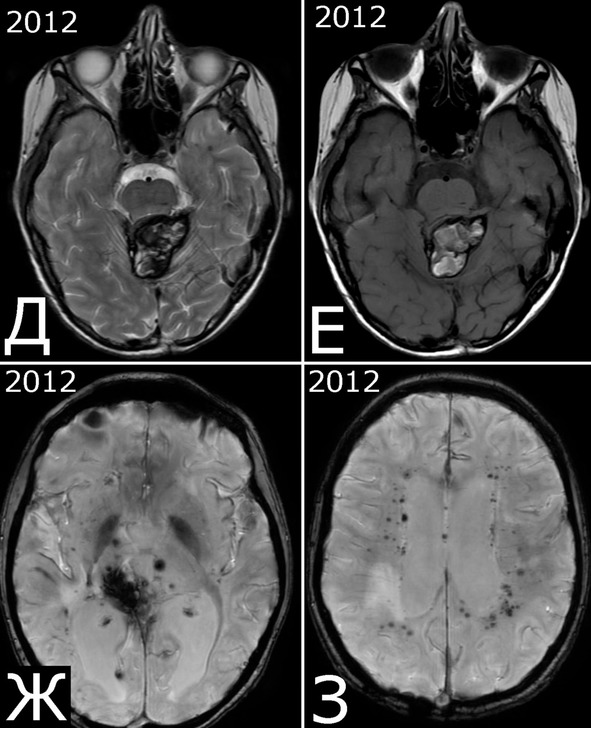

Рис. 27. Радиоиндуцированные кавернозные мальформации. Б-ной С-р, 2005 г. р. Клинический диагноз: медуллобластома IV желудочка. Состояние после удаления опухоли (2009 г) и адьювантной комбинированной терапии (лучевая терапия, 5 курсов химиотерапии). Радиоиндуцированные КМ. А, Б – 2009 г: крупная опухоль IV желудочка. МРТ, режимы Т1 и Т2. В, Г – 30.05.12г: при контрольном обследовании выявлены два бессимптомных объемных образования в правой теменной области, по МРТ—характеристкам соответствующие сосудистой патологии (радиоиндуцированные КМ?). Признаков рецидива опухоли нет. Д, Е – 10.05.13 г.: при контрольном обследовании объем и структура сосудистых образований остаются прежними. Учитывая отсутствие клинических симптомов, хирургическое вмешательство не проводили